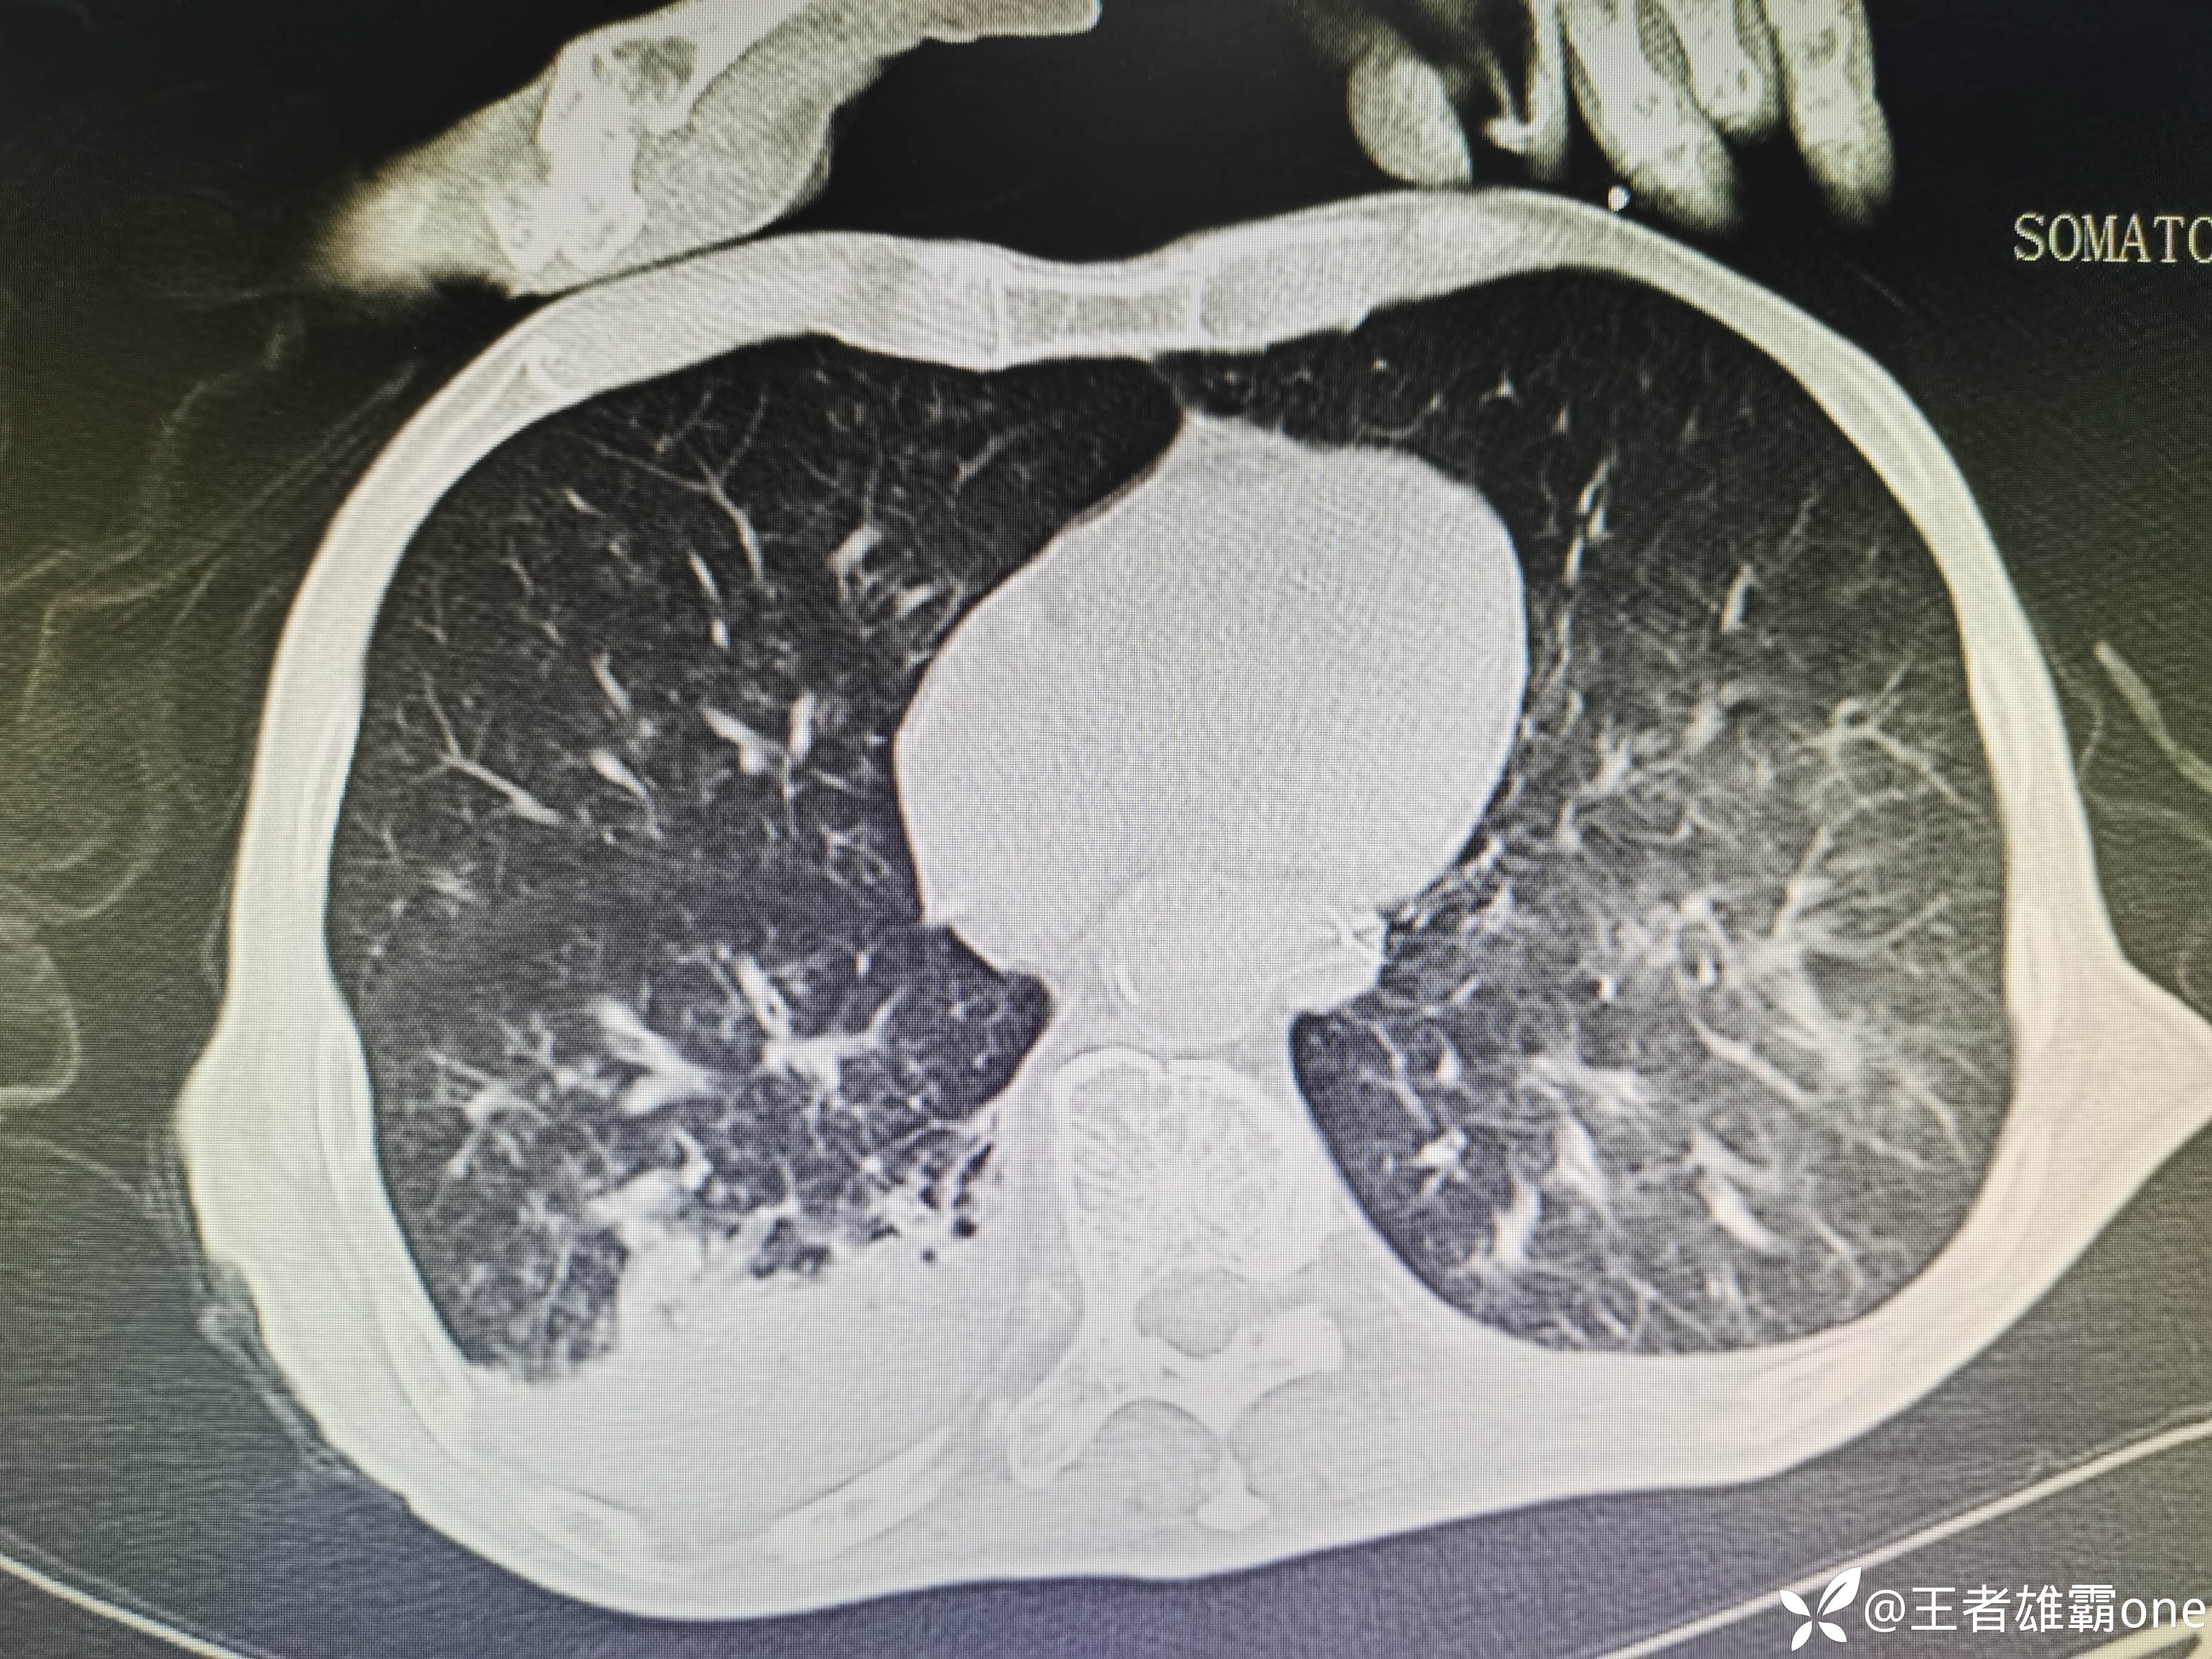

入院时胸部CT:

具体图片:

患者呼吸机通气下氧合通气稳定(FiO2:40%,PEEP:5cmH2O)。